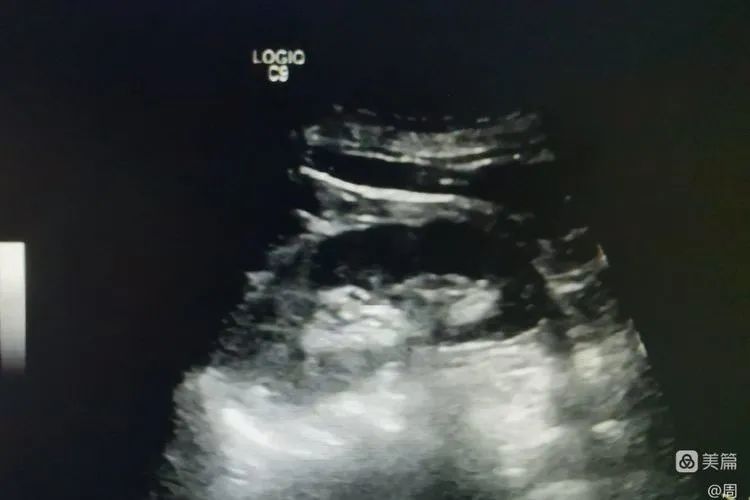

聚桂醇反复冲洗囊腔

术后囊肿消失